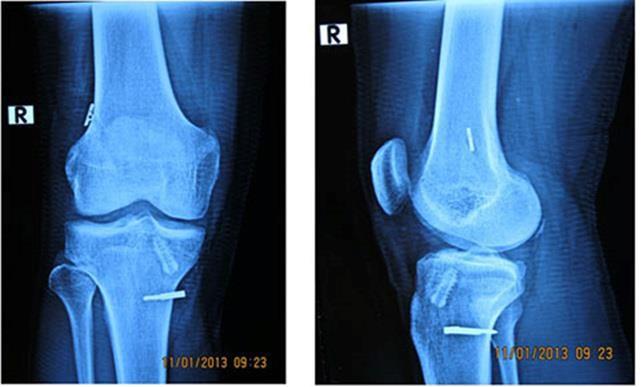

Klasik konvansiyonel Röntgen: Akut ön çapraz bağ yırtığının tanısında bulgu vermez iken, kronik yırtıklarda bazı indirekt bulgular ile ön çapraz bağ yırtığından şüphelendirebilir. Günümüzde en kolay ve en net bulgu veren görüntüleme yöntemi MR dır, MR ile %93-98 arasında tanı konulabilirken MR menisküs yırtığı, kıkırdak lezyonu ve diğer bağ yırtığı gibi ek yaralanmalarında saptanmasını sağlar.